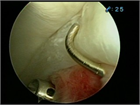

1. 単純X線撮影と読影のポイントを追加し、大腿骨寛骨臼インピンジメント(FAI)の疫学・関節症性変化への進行に関する最新の文献を参考に加筆した。

1. 保存治療、手術治療に関するエビデンスを最新の文献を参考に加筆した。

1. 典型症例と難治症例の自験例を追加した。